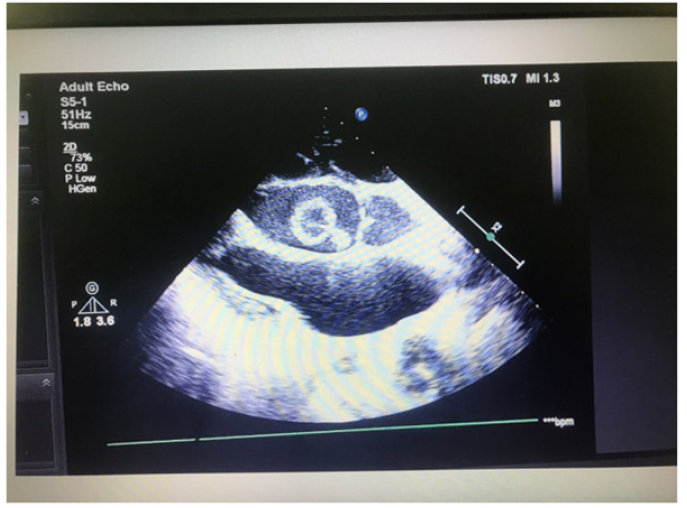

Figure 3 is echocardiogram. It demonstrated a ring-shaped mass attached to aortic valve and its convexity towards left ventricle. Left ventricle was dilated with features of moderate mitral regurgitation and aortic regurgitation. As we did not see the ring-shaped mass attached to aortic valve, we traced the similar photo in internet. It was similar appearance with aneurysm of sinus of Valsalva.

Figure 3a: Echocardiogram demonstrating a ring-shaped mass attached to aortic valve and its convexity towards left ventricle.

Figure 3b: Echocardiogram demonstrating a ring-shaped mass attached to aortic valve and its convexity towards left ventricle.